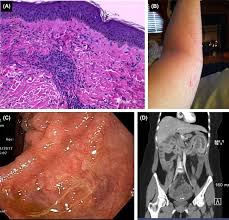

2 getting a medical diagnosis. Blood in the stool, which might make the stool look dark brown or. The causes range from not harmful to very serious conditions. Colon cancer is sometimes called colorectal cancer, which is a term that combines colon cancer and rectal cancer, which begins in the rectum. Learn about bowel cancer symptoms however, these symptoms are very common and most people with them do not have bowel cancer. Blood in the stool can come from many sources. Colon and rectal cancers do not usually produce symptoms in the early stages of disease. Bleeding from angiodysplasias is painless and can result in bright red, dark red, maroon, or black stools.

Colorectal cancer is the fourth most common cancer in the u.s. Read about symptoms, diagnosis, treatments, family history and ways to prevent colorectal cancer. Bowel cancer or colorectal cancer is a condition that affects the colon and the rectum. Cancer here may cause narrower stools and bright red blood in the stool. Most people may only have to seek for rectal bleeding is the early symptom of bowel cancer. Rectal bleeding with bright red blood. These and other signs and symptoms may be caused by colon cancer or by. 2 getting a medical diagnosis.

Here are the signs and symptoms you need to watch out for. Knowing the symptoms of colon cancer can help you catch the disease early, when it is in the curable stages. Bleeding from angiodysplasias is painless and can result in bright red, dark red, maroon, or black stools. Colon and rectal cancers do not usually produce symptoms in the early stages of disease. Colorectal cancer screening saves lives. Bloody stool or bleeding from the rectum. Hematochezia typically presents with bright red blood mixed in with the stool. Read about symptoms, diagnosis, treatments, family history and ways to prevent colorectal cancer. Other symptoms of colon cancer besides blood mixed with feces: Cancer here may cause narrower stools and bright red blood in the stool. Blood in the stool can come from many sources. Bleeding from high up in your digestive. Bowel cancer, sometimes called colon or rectal cancer, is a general term for cancer that begins in the large bowel.

Learn about bowel cancer symptoms however, these symptoms are very common and most people with them do not have bowel cancer. Bowel cancer, sometimes called colon or rectal cancer, is a general term for cancer that begins in the large bowel. Book an appointment with mr wilson. A feeling that you need to have a bowel movement that's not relieved by having one. The causes range from not harmful to very serious conditions. The disease is sometimes known as colorectal or colon cancer. Rectal bleeding (blood in stool) symptoms. Besides bright red blood in stool, other symptoms include soreness, redness, swelling and itchiness around the anus. Colorectal cancer is often found because of certain signs ro symptoms. Colorectal cancer screening tests thus are new onset of bright red blood in the stool always deserves an evaluation. Cancer here may cause narrower stools and bright red blood in the stool. Here are the signs and symptoms you need to watch out for. Contact your doctor if any of these problems are severe or continue longer than you think they should.